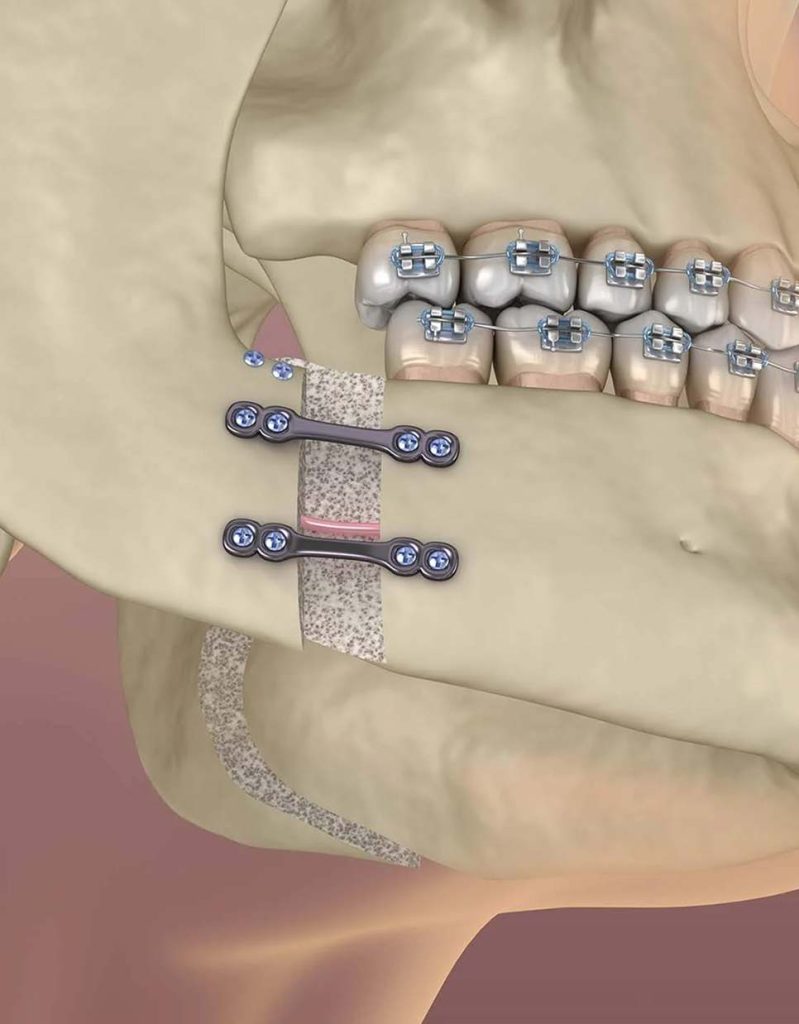

Orthognathic Surgery:

Reconstructing Structural Harmony

When complex dental misalignments cannot be resolved through standard orthodontics alone, our maxillofacial specialists and orthodontists collaborate to perform orthognathic surgery. This advanced discipline is reserved for patients who have fully completed their bone development and require significant skeletal correction. Whether addressing genetic deformations or trauma related issues, this surgery resolves functional challenges such as breathing difficulties, impaired pronunciation, and inefficient chewing.

Our elite surgical team utilizes advanced computerized simulation software to map out every detail of your single jaw or double jaw correction. This digital planning ensures that every structural adjustment prioritizes both elite physical appearance and flawless practical function. Following the procedure, a dedicated monitoring phase of several months ensures that your new skeletal foundation achieves absolute stability and perfect facial symmetry.